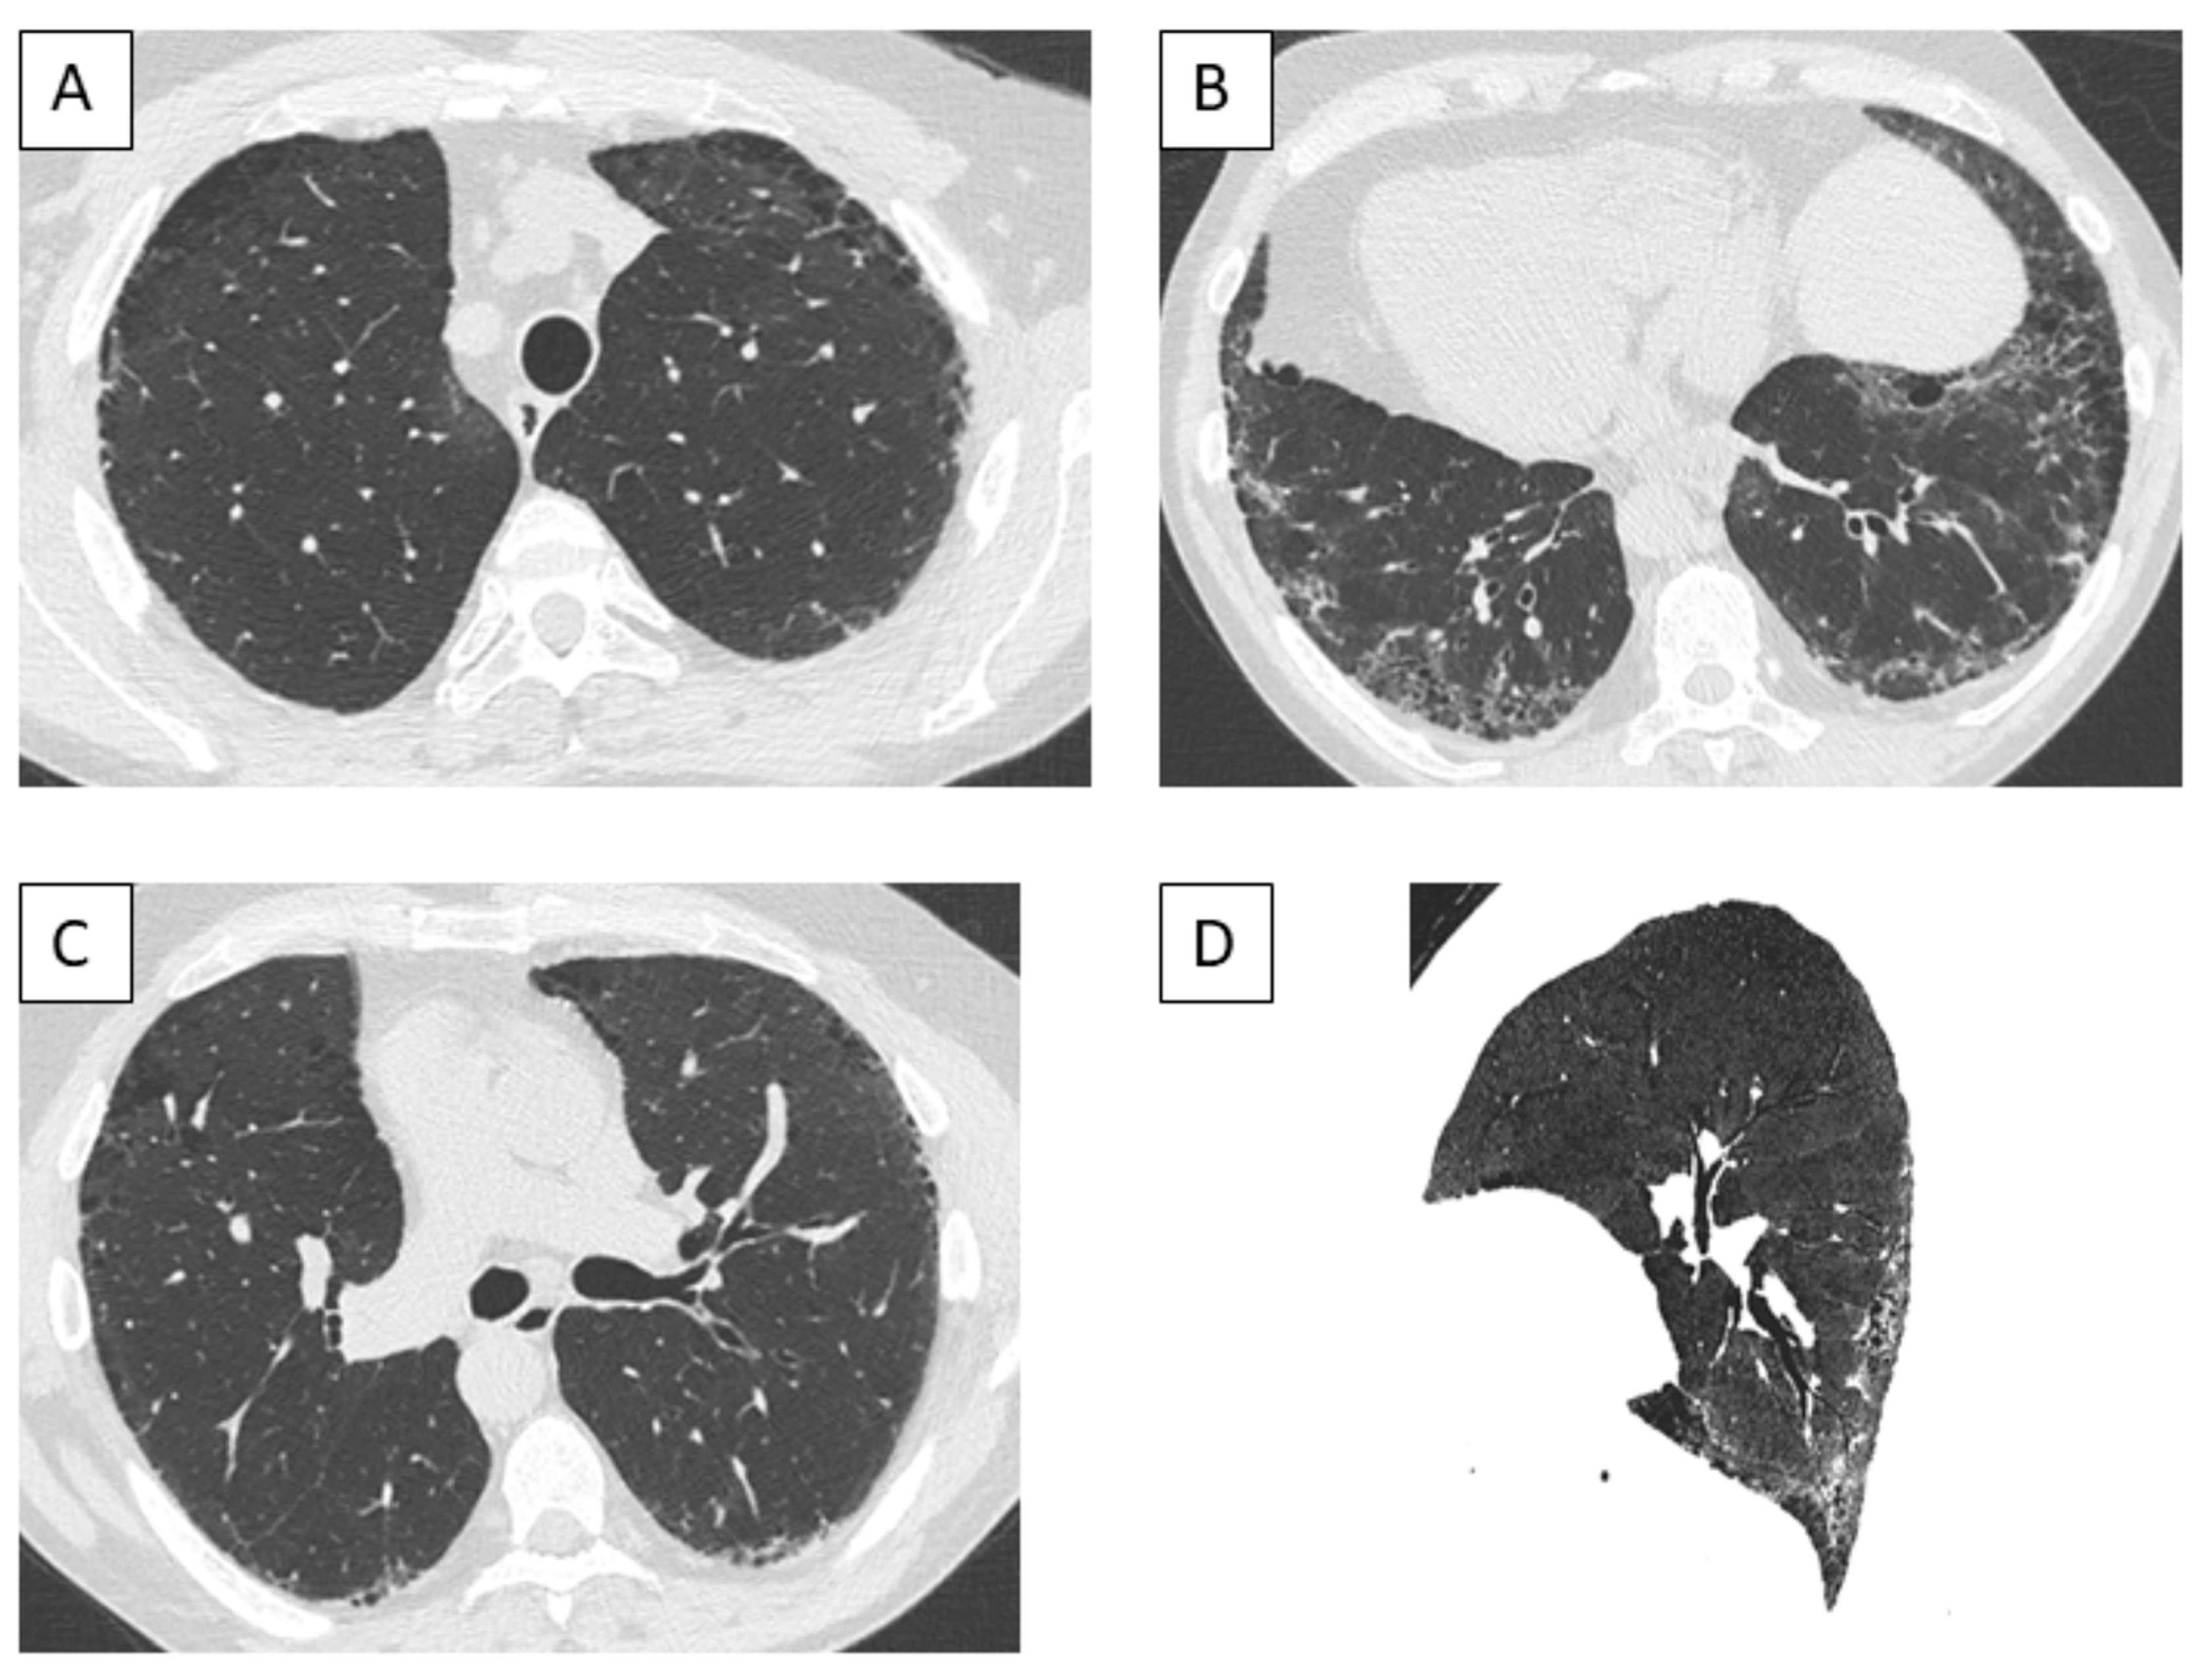

3.6. Imaging Findings

3.7. Bronchoalveolar Lavage